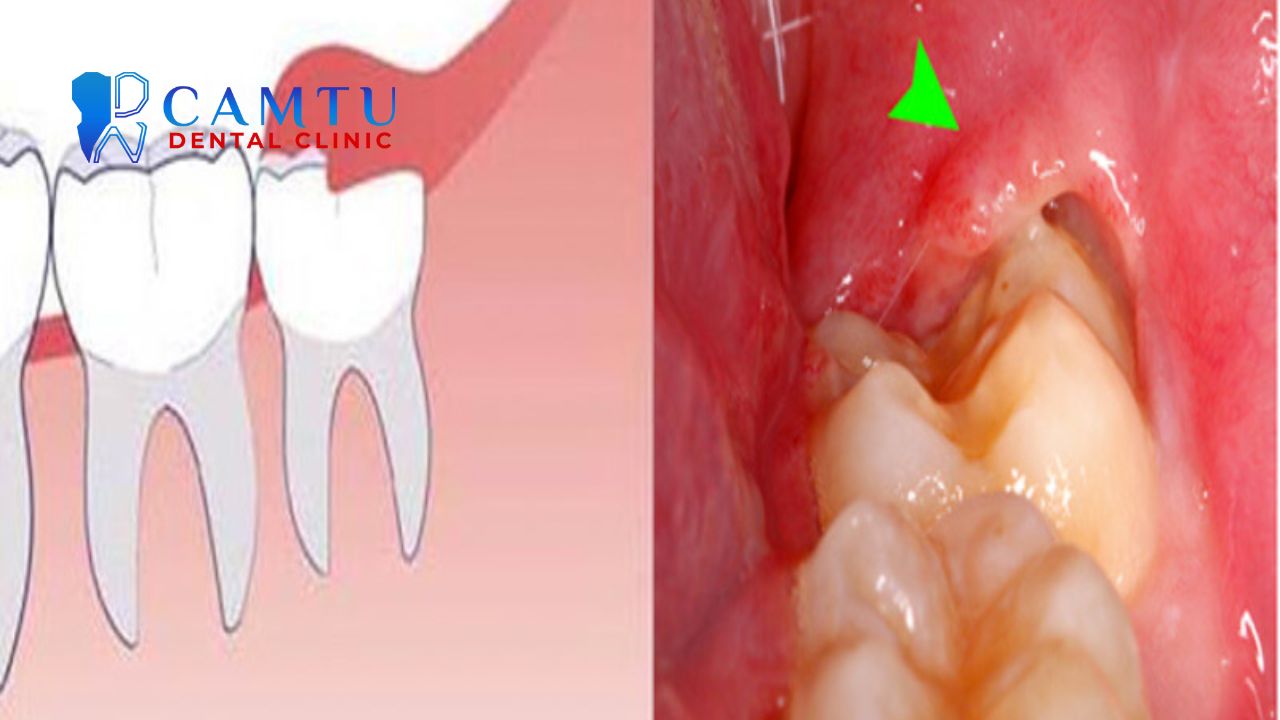

Răng khôn mọc lệch, mọc ngầm hoặc mọc kẹt trong xương hàm thường khó nhổ hơn so với răng mọc thẳng. Khi phải can thiệp sâu vào xương và mô mềm, nguy cơ sưng đau, viêm ổ răng khô và nhiễm trùng sau nhổ răng khôn sẽ tăng lên.

Ngoài ra, răng khôn nằm gần dây thần kinh hoặc xoang hàm trên có thể làm tăng nguy cơ tổn thương thần kinh hoặc thủng xoang. Những trường hợp này cần được đánh giá kỹ bằng phim chụp trước khi nhổ răng.